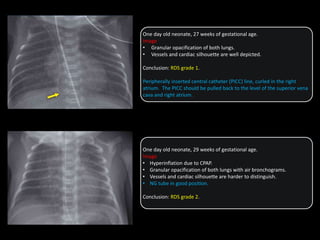

One day old neonate, 27 weeks of gestational age.

Image

• Granular opacification of both lungs.

• Vessels and cardiac silhouette are well depicted.

Conclusion: RDS grade 1.

Peripherally inserted central catheter (PICC) line, curled in the right

atrium. The PICC should be pulled back to the level of the superior vena

cava and right atrium.

One day old neonate, 29 weeks of gestational age.

• Hyperinflation due to CPAP.

• Granular opacification of both lungs with air bronchograms.

• Vessels and cardiac silhouette are harder to distinguish.

• NG tube in good position.

Conclusion: RDS grade 2.